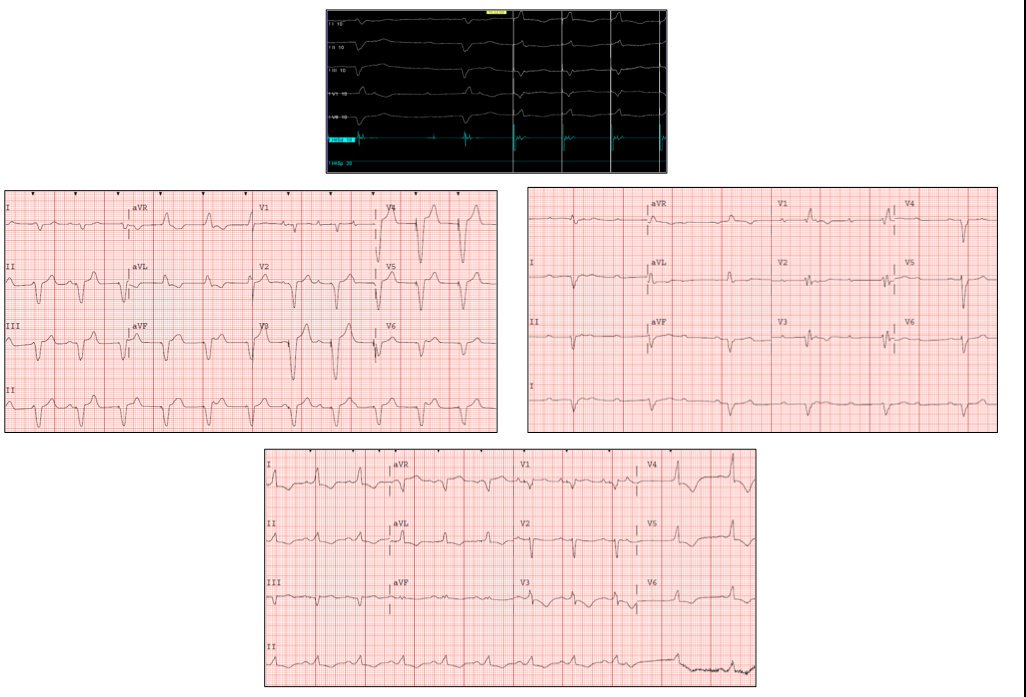

Amiloidosis TRT. Implante MP bicameral hace un año por BAV completo, con escape con morfología de BRDHH y HARI. Se nos remite por desplazamiento de electrodo AD y disfunción ventricular leve. Se realiza actualización con estimulación hisiana. Corrección de BRDHH y HARI